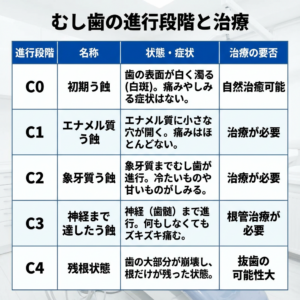

むし歯の自然治癒を理解するためには、まずむし歯がどのように進行するのかを知ることが重要です。

むし歯は進行度によってC0からC4までの5段階に分類されます。このうち自然治癒が可能なのはC0のみです。C0は、歯の表面のエナメル質からミネラルが溶け出している「脱灰(だっかい)」という状態ですが、まだ物理的に穴が開いていません。

この段階であれば、後述するセルフケアによって歯を修復(再石灰化)させることが可能です。C1以降は歯に穴が開いてしまうため、治療が必要になります。